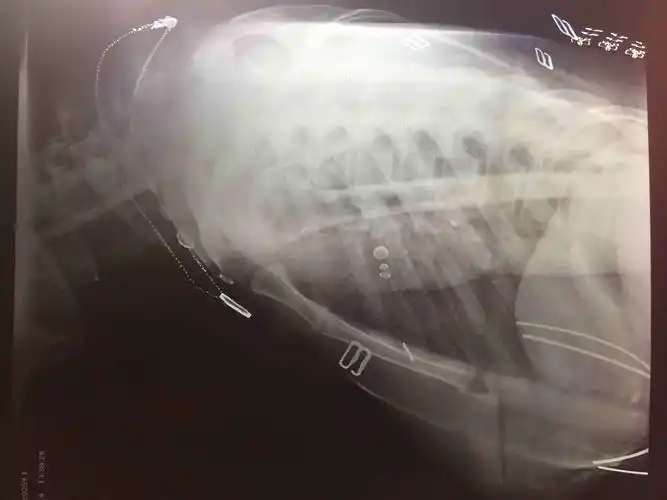

肩关节x线检查特殊体位